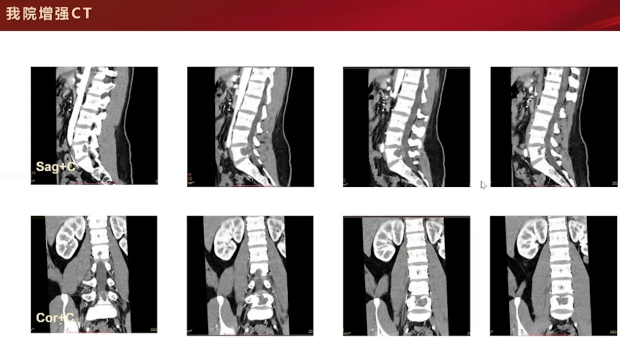

增强CT检查,在骨窗和软组织窗下可见L5后缘局部膨胀性骨质破坏,内缘呈扇贝样压迹改变,仍无明显骨膜反应。平扫时,病灶内可见斑斑点点高密度影,性质待定,可能为残存骨嵴、软骨源性钙化或骨化表现。该病例主要累及L5椎体,附件未见明显受累。增强扫描呈轻度强化,矢状位和冠状位可见病灶主要累及椎体,未累及附件。

随后的磁共振检查,T2加权像呈高信号,增强扫描可见分隔样环形轻中度强化,这些支持征象提示为软骨源性肿瘤。主要依据包括T2信号较高、膨胀性骨质破坏伴硬化边、内部点状钙化以及增强扫描呈环形和分隔样强化,综合判断为软骨肉瘤。